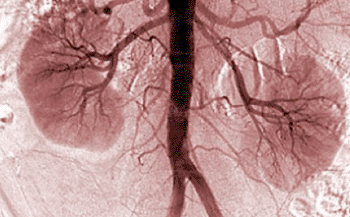

Un estudio metabolómico encontró que los pacientes con enfermedad renal crónica (ERC), expresaban un grupo de 13 metabolitos de biomarcadores que los diferenciaban de los individuos sanos.

Investigadores de la Universidad de California, San Diego (EUA) y la compañía biomédica ClinMet (San Diego, CA, EUA) colaboraron en un estudio para identificar biomarcadores fiables en la orina de los pacientes con ERC. El estudio se llevó a cabo usando la plataforma de análisis de metabolómica clínica, patentada, de ClinMet.

Se usó la cromatografía de gases - espectrometría de masas para cuantificar 94 metabolitos en la orina de 193 pacientes con diabetes mellitus (DM) y ERC (DM + ERC), en pacientes con DM sin ERC (DM -CKD) y en los controles sanos. Los resultados revelaron que, en comparación con los niveles en los controles sanos, 13 metabolitos estaban reducidos significativamente en las cohortes DM + ERC, y 12 de los 13 seguían siendo significativos cuando se comparaban con la cohorte DM- ERC. Muchos de los metabolitos expresados diferencialmente fueron aniones orgánicos solubles en agua.

El análisis de los datos de bioinformática indicó que 12 de los 13 metabolitos expresados diferencialmente estaban relacionados con el metabolismo mitocondrial y sugirió la posibilidad de la supresión global de la actividad mitocondrial en la enfermedad renal diabética. Apoyando este análisis, se encontró que las secciones del riñón diabético humano expresaba menos proteína mitocondrial. Los exosomas urinarios de pacientes con diabetes y enfermedad renal crónica tenían menos ADN mitocondrial, y los tejidos renales de pacientes con enfermedad renal diabética tenían una menor expresión de los genes PGC1alfa (un regulador maestro de la síntesis mitocondrial).